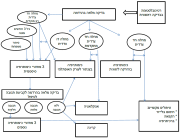

| 07:47, 12 באוגוסט 2023 | רטינובלסטומה3.png (קובץ) |  |

1.5 מגה־בייטים | Motyk | 1 | |

| 07:42, 12 באוגוסט 2023 | רטינובלסטומה 2.png (קובץ) |  |

79 קילו־בייטים | Motyk | 1 | |

| 18:29, 11 באוגוסט 2023 | רטינובלסטומה1.png (קובץ) |  |

83 קילו־בייטים | Motyk | 1 | |

| 05:34, 11 באוגוסט 2023 | INRG 2.png (קובץ) |  |

216 קילו־בייטים | Motyk | 1 |